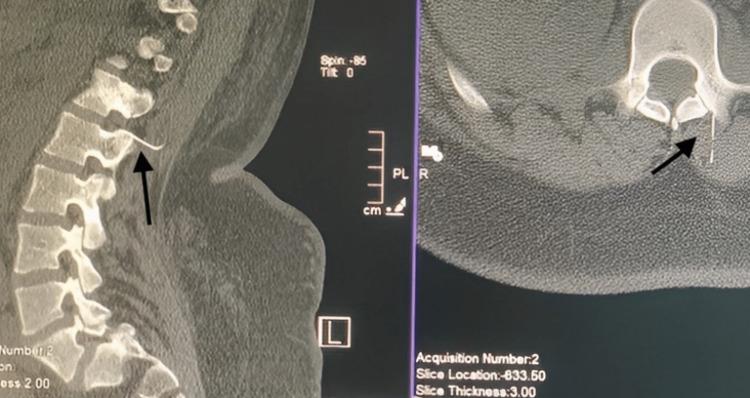

Spinal anesthesia is the most common mode of anesthesia utilized during caesarian sections worldwide. Despite its many advantages over general anesthesia in the pregnant cohort, uncommon and even catastrophic complications could occur due to patient-related, equipment-related, and procedure-related complications. One such uncommon event of a broken spinal needle during failed spinal anesthesia for a caesarian section and subsequent successful management is described here.

脊髓麻醉是全球剖宫产手术中最常用的麻醉方式。尽管在孕妇群体中,它相对于全身麻醉有诸多优势,但由于患者相关、设备相关和操作相关的并发症,仍可能发生罕见甚至灾难性的并发症。本文描述了一例剖宫产脊髓麻醉失败时脊髓穿刺针折断,随后成功处理的罕见事件。